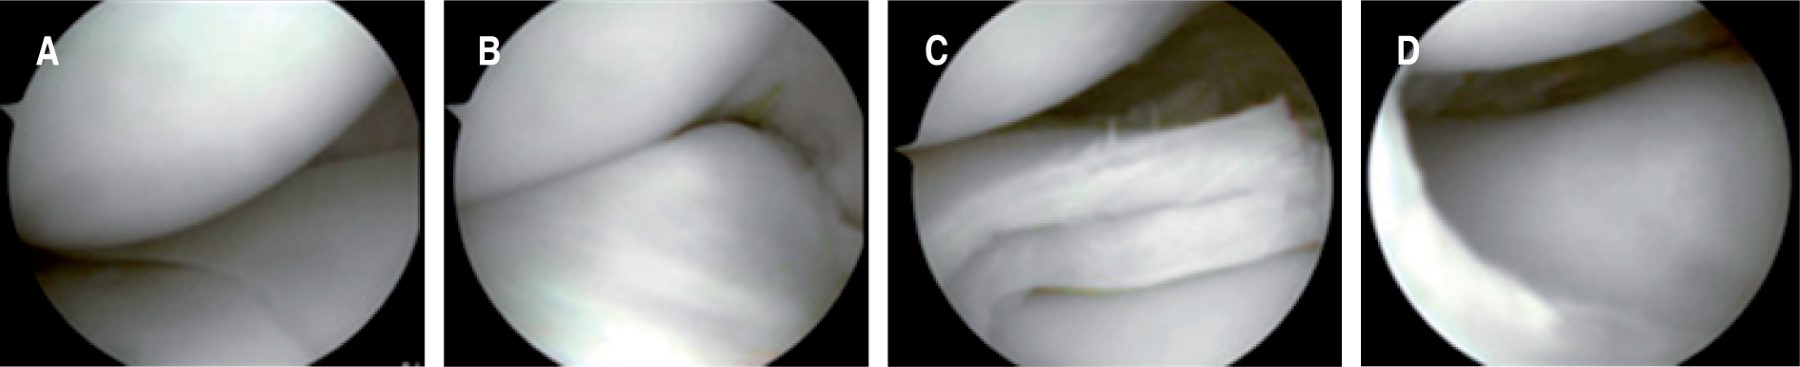

• 3. Saucerización meniscal (meniscoplastia) por vía artroscópica.

• Se refiere a la extirpación específica de la porción central de un menisco discoide, rebajando su grosor para aproximarse a la estructura anatómica normal, dejando un borde periférico intacto de forma semilunar de 6 a 8 mm de ancho, dado que esto mantiene la función del menisco evitando el desgarro y los síntomas persistentes asociados con remanentes más grandes (Figura 6).74 Es el tratamiento de elección para meniscos discoides estables, completos o incompletos, sintomáticos. Sin embargo, no se ha comparado esta técnica por grupos de edad.

• 4. Reparación meniscal por vía artroscópica.

• La reparación se refiere a la reinserción del borde meniscal periférico (posterior, central o anterior) a la cápsula a nivel tibial cuando existe inestabilidad (Watanabe tipo III o variante de Wrisberg) o a la sutura de cualquier lesión del borde vascularizado.73

En las lesiones horizontales que se extienden hacia la periferia, es necesario resecar la porción inferior o superior del menisco, dejando el borde que mantiene la inserción periférica, es decir, la porción estable (Figura 7).75

Ng y cols, concluyen que la saucerización conduce a buenos resultados a mediano y largo plazo en niños o adolescentes y que los resultados después de la saucerización sola versus la saucerización con reparación (cuando está indicado) son comparables en términos de rango de movimiento, dolor y tasas de complicaciones (Figura 8).54